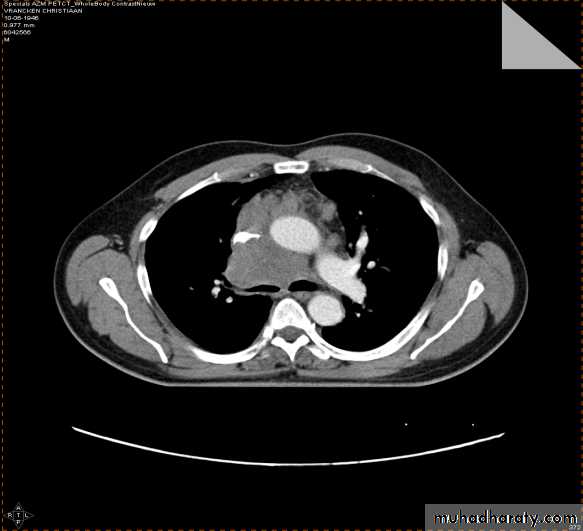

2-CT scan: indications:

• Assessment of trauma and emergency conditions.• assessment of masses( primary & secondary).

• Diagnosis Of interstitial disease.(HRCT...High resolution CT )

• guided procedures.

• CT angiography in suspected pulmonary embolism.

mediastinal window bone window lung window

4-PET CT SCAN: its main indication in diagnosis of tumor recurrence after treatment, by demonstrating of increased metabolic level in abnormal tissue. majority of malignant tumors show a greater uptake of the radioactive tracer.

PET

CT

PET/CT